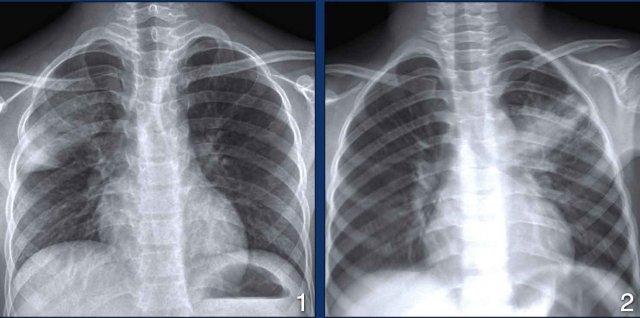

Ở trẻ nhỏ, đáp ứng miễn dịch kém trưởng thành hơn so với người lớn và bệnh lao thường biểu hiện với hạch to, tràn dịch và tổn thương vùng phổi dưới (hình phổi phải). Trước đây, điều này được cho là lao nguyên phát.

Ở người lớn có hệ miễn dịch bình thường, lao thường biểu hiện với đông đặc thùy trên và tạo hang (hình phổi trái), vốn bị chẩn đoán nhầm là lao hậu nguyên phát hoặc lao tái hoạt.

Điều này cũng giải thích tại sao ở bệnh nhân HIV có số lượng CD-4 thấp, hạch to, đông đặc thùy dưới và tràn dịch màng phổi phổ biến hơn, trong khi ở bệnh nhân HIV có số lượng CD-4 bình thường, tạo hang thùy trên phổ biến hơn.